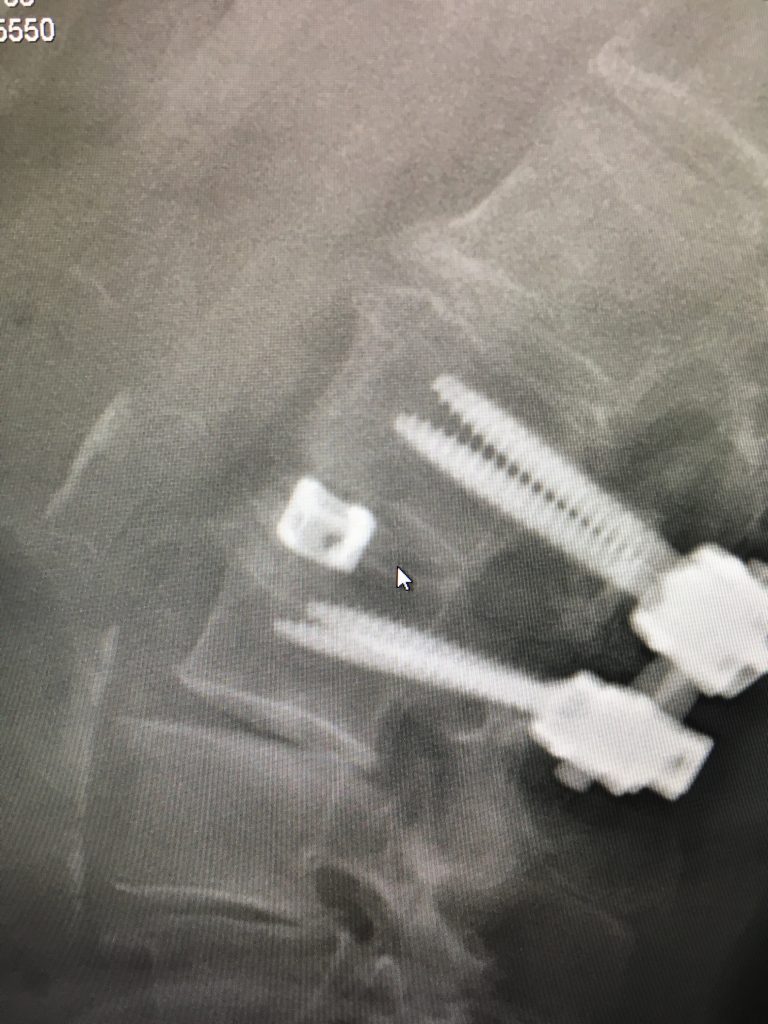

After one year of alternative therapies, including cortisone shots, nerve ablations, physical therapy, etc. to relieve referred pain that I had in my left leg, I was referred to Dr. Schwab. My pain management doctor's "bag of tricks" was in fact empty and I was advised to go forward with surgery. My husband and I interviewed 2 surgeons before we got to Dr. Schwab. At that point, I was scared and not feeling too encouraged. Meeting Dr. Schwab was like seeing a light at the end of a very dark tunnel! His calm and logical analysis totally allayed my fears and made me hopeful that I would actually be free of pain. He explained that he needed to do a fusion, opening my discs and relieving the pressure on the nerve which was clearly crushed. He also explained very clearly what I could and could not do post surgery in order to ensure its success. My surgery was a complete success- I woke up without pain and was walking 4 miles 6 days after my surgery. Not only is Dr. Schwab an incredibly gifted surgeon, he inspires complete confidence. His staff is always available via e mail or phone and the hospital experience was fabulous. I hope I will not need any other "alterations" in the future but if I do, I know who will take care of me!